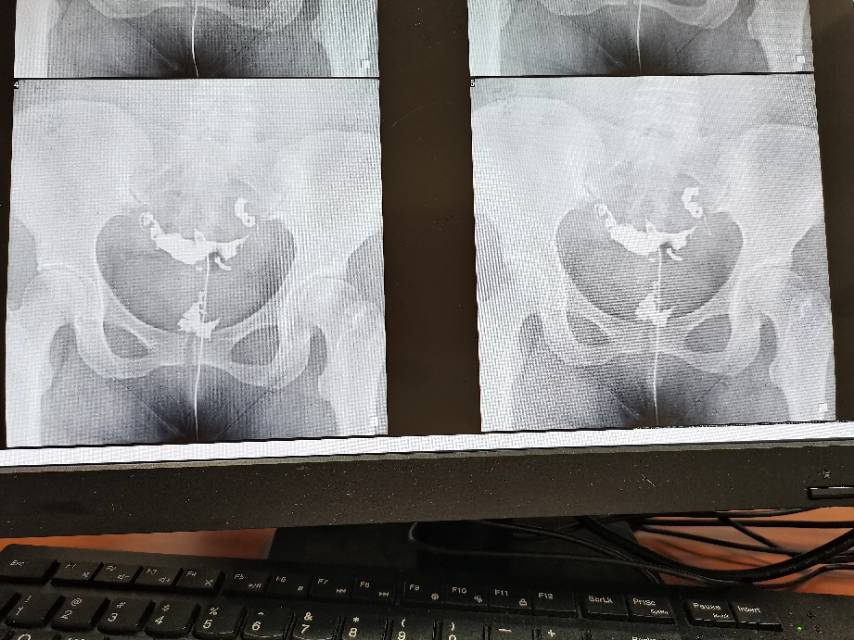

医生您好麻烦看下我的输卵管造影片影像科的报告

这种必须做手术么还是取了胚胎不是非要做

这个手术不是非得要马上做,需要根据你的年龄、生育计划等来综合评估并权衡利弊后再决定是否需要手术以及什么时候做。如果是做试管通常为了避免输卵管积液及炎症因子逆流至宫腔影响胚胎着床等,会行输卵管结扎等手术,这个手术通常在移植前完成